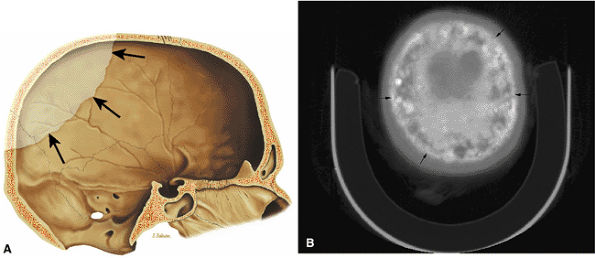

FIGURE 13.90 ● Paget—s disease of the skull. (A) Sagittal graphic illustration demonstrates an osteolytic lesion (arrows) involving the calvarium, consistent with osteoporosis circumscripta. (B) Axial CT image shows diploic widening and mixed lytic and sclerotic changes (cotton-wool appearance) (arrows) in the late stage of Paget—s disease.

|